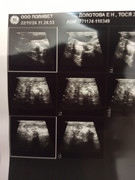

Сделали повторное узи 22.11. 2024 (первое было 09.11.2024). Высылаю фото и заключение.

Теперь ставят гидрометру и эндометрит. По мочевому мочекаменную.